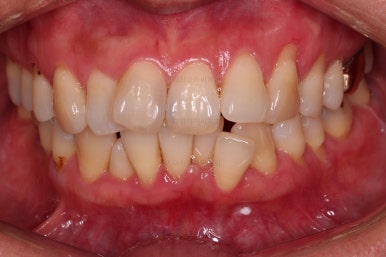

동래임플란트교정 초진 시 입안의 모습입니다.

치열이 전반적으로 삐뚤어져 있는 양상이고요.

아랫니가 윗니보다 더 많이 삐뚤어 있는데요.